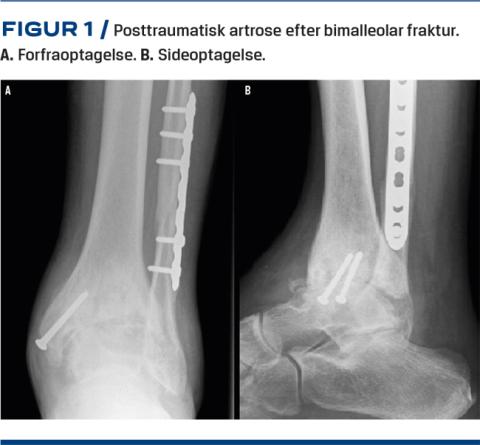

Røntgenbilleder af ankelleddet tages altid med belastning og viser typisk ledspalteafsmalning, subkondral sklerosering, eventuel fejlstilling (i både frontalt og sagittalt plan), osteofytter, påvirkning af syndesmosen eller andre tegn på tidligere frakturer. Se Figur 1 for typiske fund ved posttraumatisk artrose. Supplerende billeddiagnostik i form af CT, vægtbelastet CT, SPECT og MR-skanning kan bidrage med yderligere information. MR-skanning er den mest sensitive og specifikke noninvasive undersøgelse til vurdering af brusken i ankelleddet, mens SPECT-CT gør det muligt at korrelere morfologiske og biokemiske informationer i udredning af ankelartrose og kan hjælpe til at lokalisere isolerede læsioner i ankelleddet [7]. Figur 2 er en oversigt over udredning, visitation og behandling i Danmark.